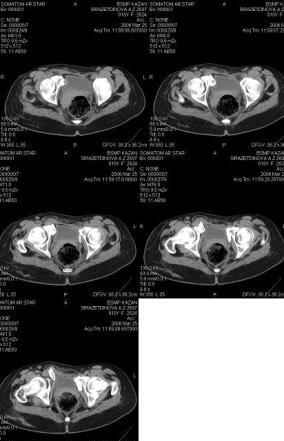

Re: Неправильно сросшийся перелом костей таза

Предоставляю срезы. Если пациентку функционально ничего не беспокоит, стоит ли навязывать ей лечение.